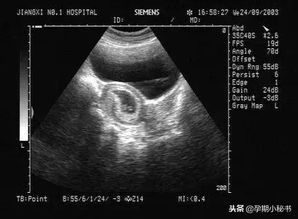

随着计算机技术的不断发展,DOS系统B超经历了从黑白到彩色、从二维到三维的演变。这一时期,DOS系统B超在临床诊断中发挥着重要作用,为医生提供了丰富的影像信息。

1. 图像质量有限:与当前先进的医学影像技术相比,DOS系统B超的图像质量存在一定差距。